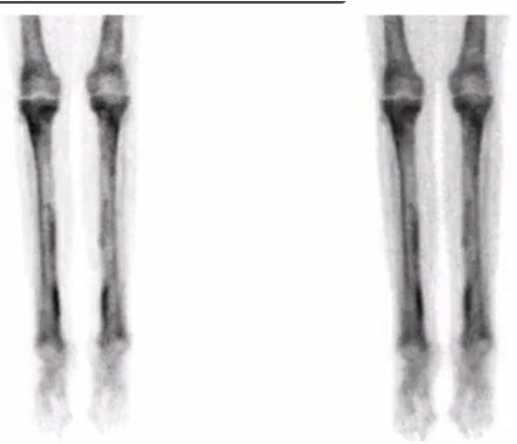

What additional imaging do you want?

CT Chest